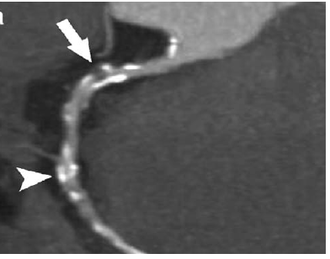

CCTA — CAD-RADS 4a Stenosis

Coronary CT angiography showing severe stenosis (70-99%) graded CAD-RADS 4a

CT Downloaded 2026-03-15

Ct

Cta Coronary 120 kVp

Wikimedia Commons: CCTA CAD-RADS 4a.png